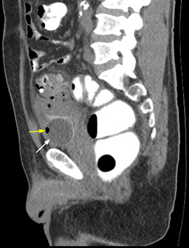

Durante manejo intrahospitalario presentó un episodio de fecaluria y neumaturia, sugestivas de FCV, se realizó cistoscopia transuretral en dónde no se evidencian trayectos fistulosos. Ante la ausencia de etiología, realizaron Tomografía Computarizada (TC) abdominopélvica con doble contraste, con hallazgos inflamatorios con aire en su interior, que evidencian la presencia de fístula colovesical asociada a enfermedad diverticular complicada (Figura 1). El paciente fue valorado por cirugía general, quienes consideraron ante clínica y hallazgos imagenológicos que requería un tratamiento quirúrgico con cierre del orificio fistuloso.

Figura 1 Tomografía axial computarizada abdominopélvica: corte sagital en donde se evidencia divertículo a nivel colónico, absceso pericólico bien (Flecha blanca), con burbuja de aire en su interior (Flecha amarilla)